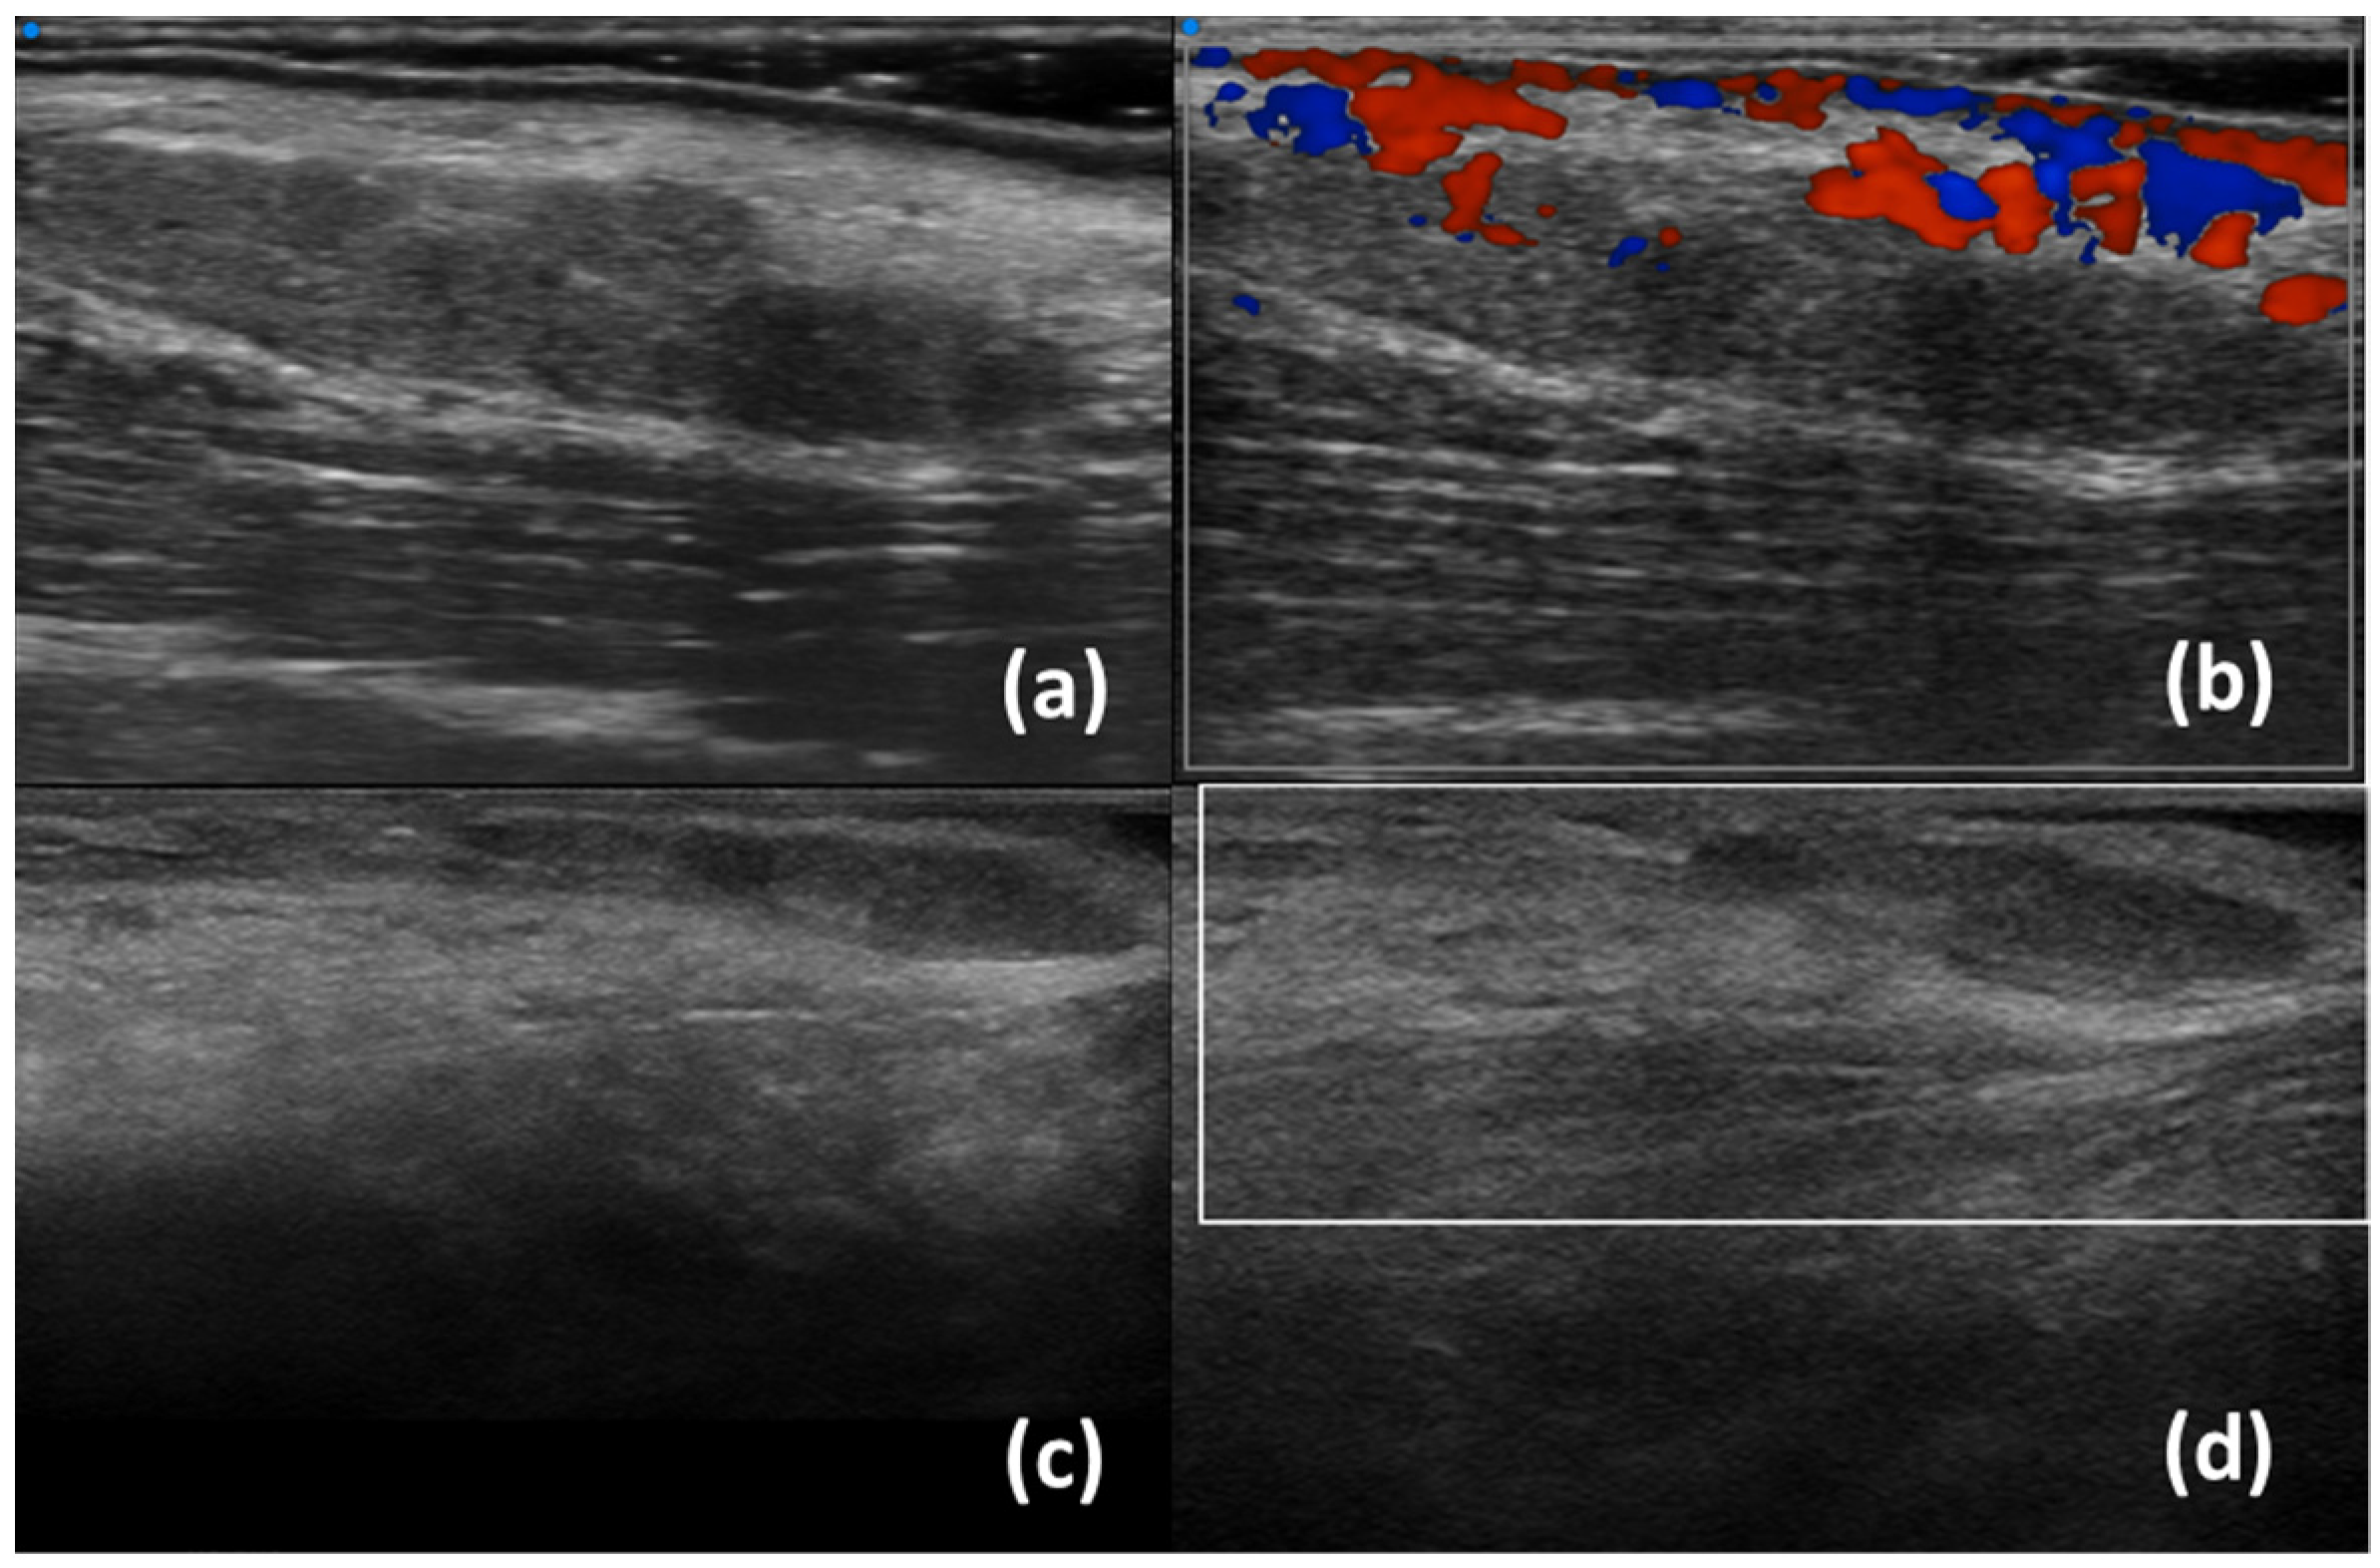

| Ferro et al. (2020) [35] | B-mode | SjD diagnostic value (SjD patients have higher inhomogeneity) Associations of inhomogeneity with Ro/SSA+ positivity Correlationsof inhomogenity with histological inflammation |

- Ferro, F.; Izzetti, R.; Vitali, S.; Aringhieri, G.; Fonzetti, S.; Donati, V.; Dini, V.; Mosca, M.; Gabriele, M.; Caramella, D.; et al. Ultra-high frequency ultrasonography of labial glands is a highly sensitive tool for the diagnosis of Sjögren’s syndrome: A preliminary study. Clin. Exp. Rheumatol. 2020, 38 (Suppl. S126), 210–215. [Google Scholar]

- Izzetti, R.; Fulvio, G.; Nisi, M.; Gennai, S.; Graziani, F. Reliability of OMERACT Scoring System in Ultra-High Frequency Ultrasonography of Minor Salivary Glands: Inter-Rater Agreement Study. J. Imaging 2022, 8, 111. [Google Scholar] [CrossRef]

- Fulvio, G.; Ferro, F.; Izzetti, R.; Governato, G.; Fonzetti, S.; La Rocca, G.; García, I.C.N.; Donati, V.; Mosca, M.; Baldini, C. POS1461 advantages of doppler in labial salivary gland ultra-high frequency ultrasound: Correlations with histological inflammation, pSS diagnosis, disease activity, and prognosis. Ann. Rheum. Dis. 2023, 82 (Suppl. S1), 1085. [Google Scholar] [CrossRef]